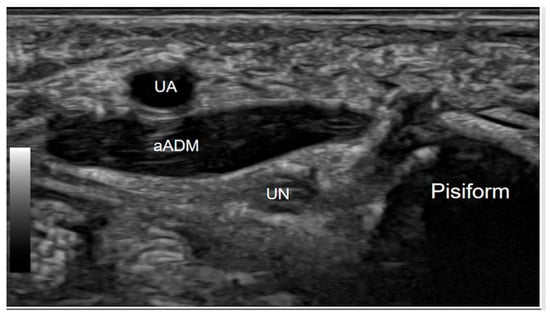

This is an anatomical variant in the hand, where an extra muscle lies adjacent to the ulnar nerve as it passes through Guyon’s canal. This muscle variant can contribute to ulnar nerve compression within the canal, potentially leading to symptoms of ulnar neuropathy, such as numbness, tingling, or weakness in the ring and small fingers. Clinically, the presence of this muscle can complicate the diagnosis and management of ulnar nerve entrapment at Guyon’s canal, as it may mimic or exacerbate symptoms associated with other pathologies such as ganglion cysts or lipomas. The dynamic ultrasound assessment of this condition is particularly valuable. By having the patient actively abduct the fifth finger, real-time visualisation of the accessory abductor digiti minimi contraction and the ulnar nerve entrapment or compression at Guyon’s canal becomes possible. This dynamic evaluation is crucial for distinguishing between the asymptomatic presence of the accessory muscle and its pathological variant [12]. Identifying this variant on imaging or during surgical exploration is essential for appropriate management, as decompression or careful dissection around the muscle may be necessary to alleviate nerve compression symptoms effectively (Figure 4).

Figure 4.

Axial Gray-scale Ultrasound image at the level of the proximal Guyon’s canal, at the level of the pisiform bone, demonstrates an anatomical variant where an accessory abductor digiti minimi muscle (aADM) overlies the canal. The ulnar nerve (UN) is present within the canal, while the ulnar artery (UA) is positioned volar to the accessory muscle.